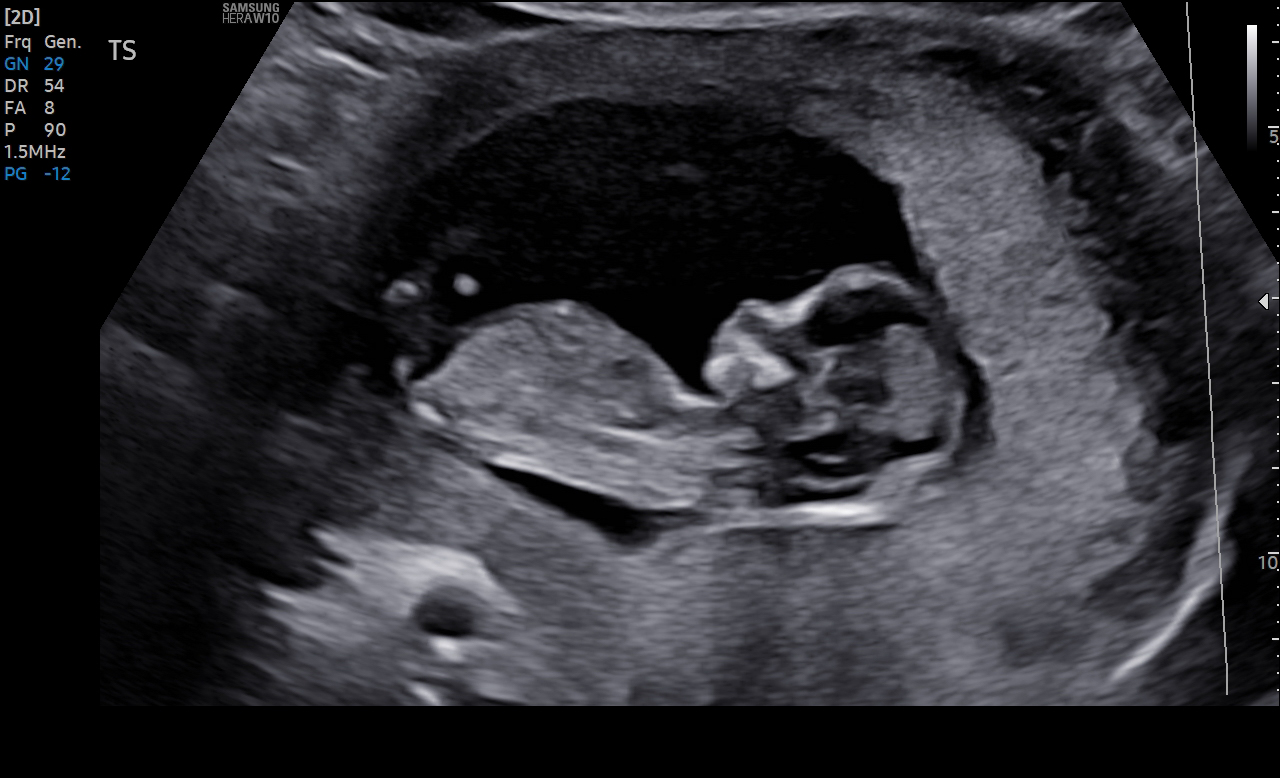

In surrogacy, the biggest moment for everyone is the heartbeat confirmation. This is the moment when the intended parents and surrogate have a confirmed pregnancy.

This is also the start of the large compensation payments for the surrogate. A lot of time and effort has been put into getting to this moment, and now everyone can breathe a sigh of relief that it worked.